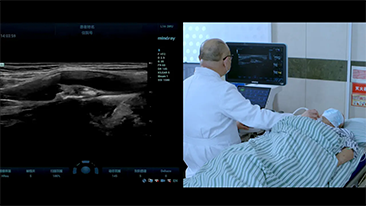

As solu??es de imagem geral Mindray Resona ajudam mĂŠdicos a obter resultados mais precisos e eficientes de diagnĂłstico e tratamento por meio de sondas de aplica??o de subdivis?es abrangentes e ferramentas eficientes de aplica??o clĂnica.

O ambiente mĂŠdico atual se tornou mais complexo, com um nĂşmero crescente de casos difĂceis e cargas de trabalho.